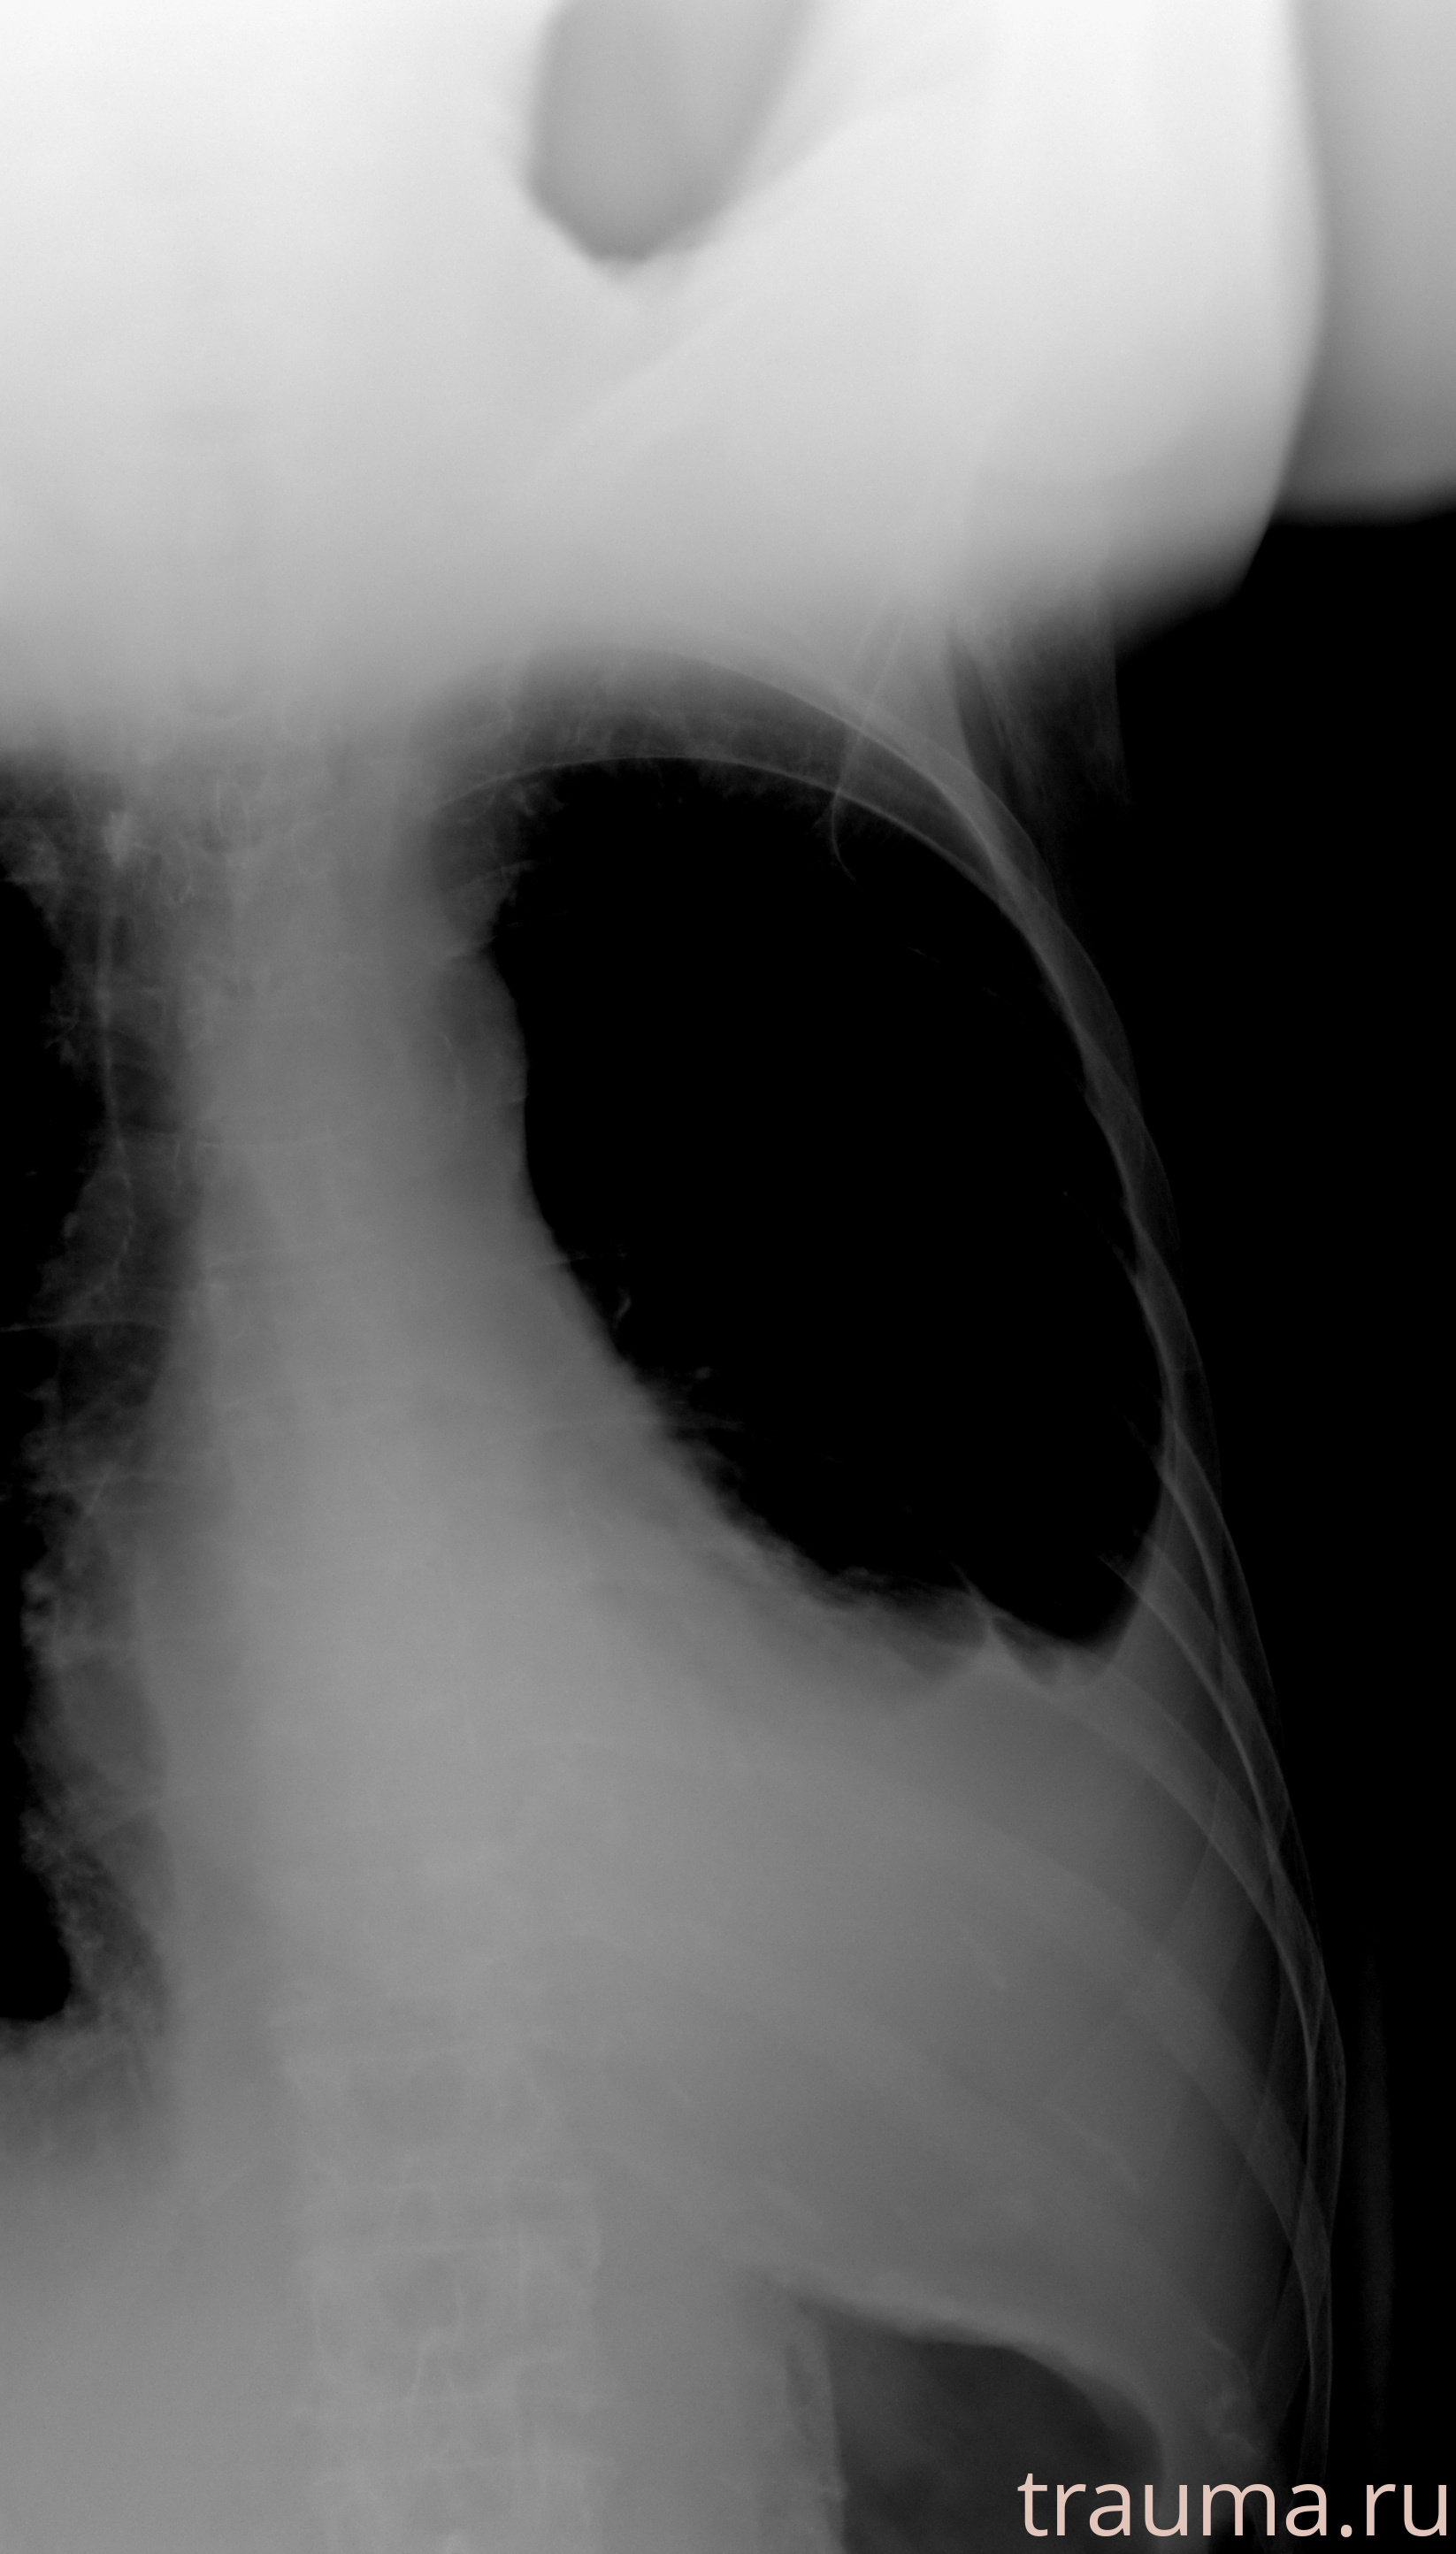

Рентген на дому: по вашему адресу приезжает врач-рентгенолог, травматолог-ортопед с мобильным рентгеновским аппаратом, проводит диагностику травмы или заболевания, делает необходимые рентгенограммы, дает рекомендации по дальнейшему лечению. Получить качественные снимки в домашних условиях возможно благодаря уникальной методике, разработанной МосРентген Центром для института  Склифосовского